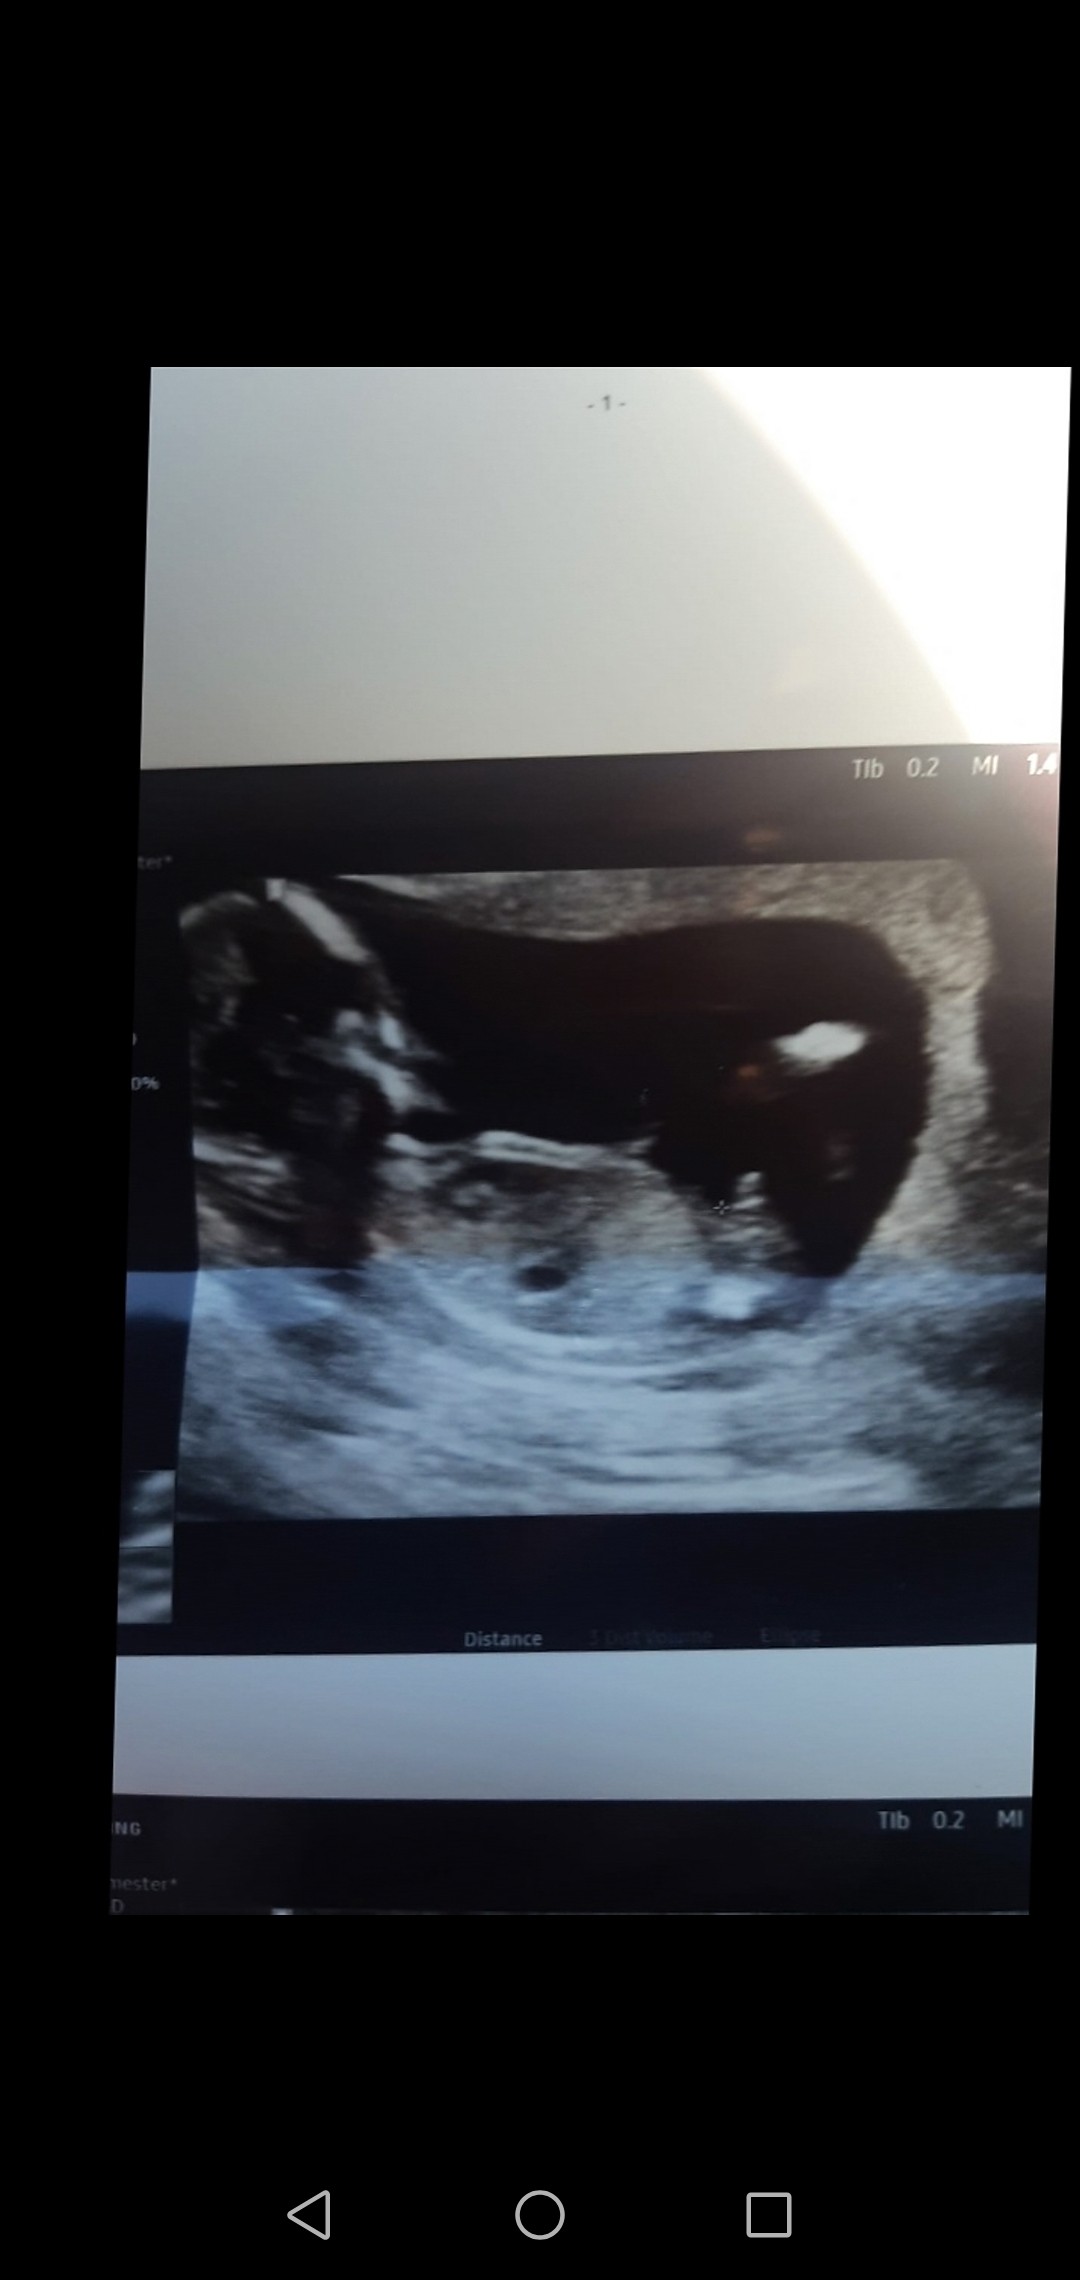

Wystawił się w pełni na usg 😂

Załączniki

• Screenshot_20210909_092025_com.android.gallery3d.jpg

Screenshot_20210909_092025_com.android.gallery3d.jpg

141,8 KB · Wyświetleń: 110